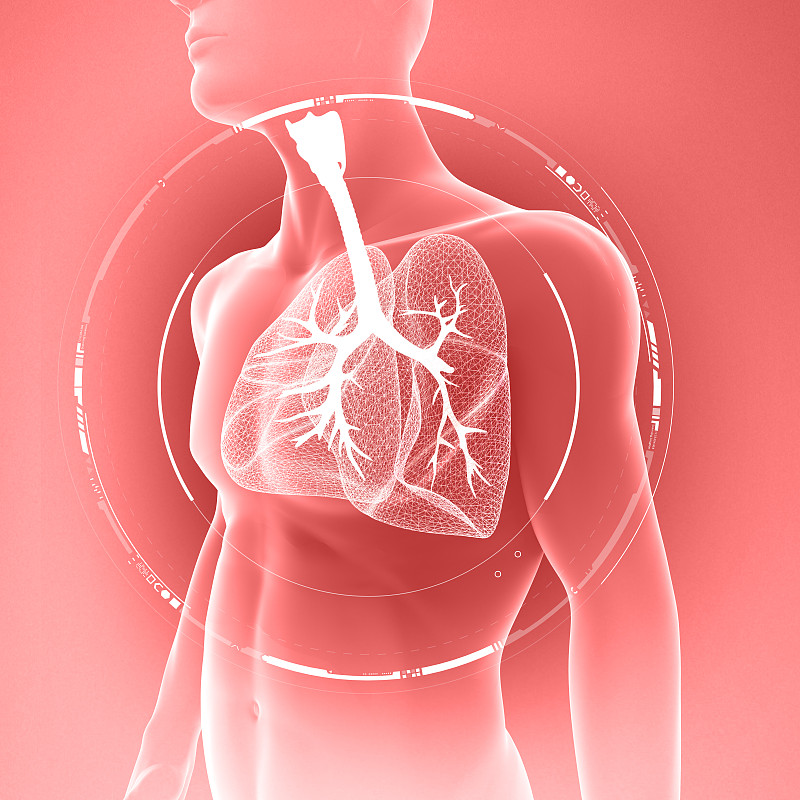

人体呼吸系统肺解剖学详情

JPG

人体呼吸系统肺解剖学详情

JPG

胸腔前视图中的肺详情

JPG